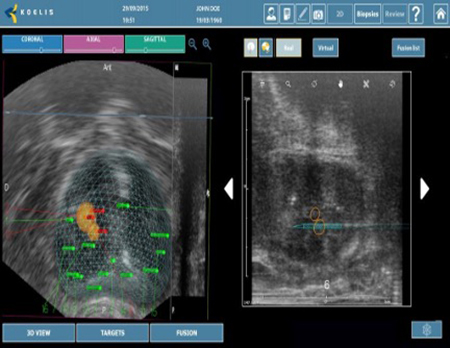

Το τελευταίας τεχνολογίας σύστημα πλοήγησης Koelis TRINITY PERINE σε συνδυασμό με την άρτια επιστημονική κατάρτιση και εξειδίκευση του ιατρικού μας προσωπικού του τμήματος βιοψίας προστάτη, καθιστούν τον όμιλο ΙΑΤΡΟΠΟΛΙΣ τον μοναδικό στην Ελλάδα, που έχει την δυνατότητα βιοψίας ελαστικής σύντηξης μέσω διαπερινεϊκής προσπέλασης, υπό τοπική αναισθησία.

Koelis Trinity Perine

Υπερσύγχρονη πλατφόρμα πλοήγησης που επιτρέπει:

- Την ελαστική συγχώνευση τρισδιάστατων εικόνων Υπερηχογραφήματος και Μαγνητικής Τομογραφίας σε πραγματικό χρόνο μέσω του λειτουργικού συστήματος εντοπισμού Organ-Based Tracking Fusion( OBT Fusion).

- Aπεικόνιση του προστάτη σε τρισδιάστατη μορφή.

- Λήψη βιοψίας σε εικονικό και πραγματικό χρόνο

- Αναλυτική χαρτογράφηση της βιοψίας προστάτη.

- Δυνατότητα ανάκλησης των στοιχείων της βιοψίας για περαιτέρω μελέτη (follow up)